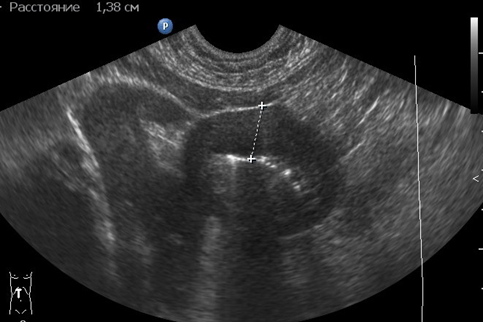

- УЗИ органов брюшной полости.